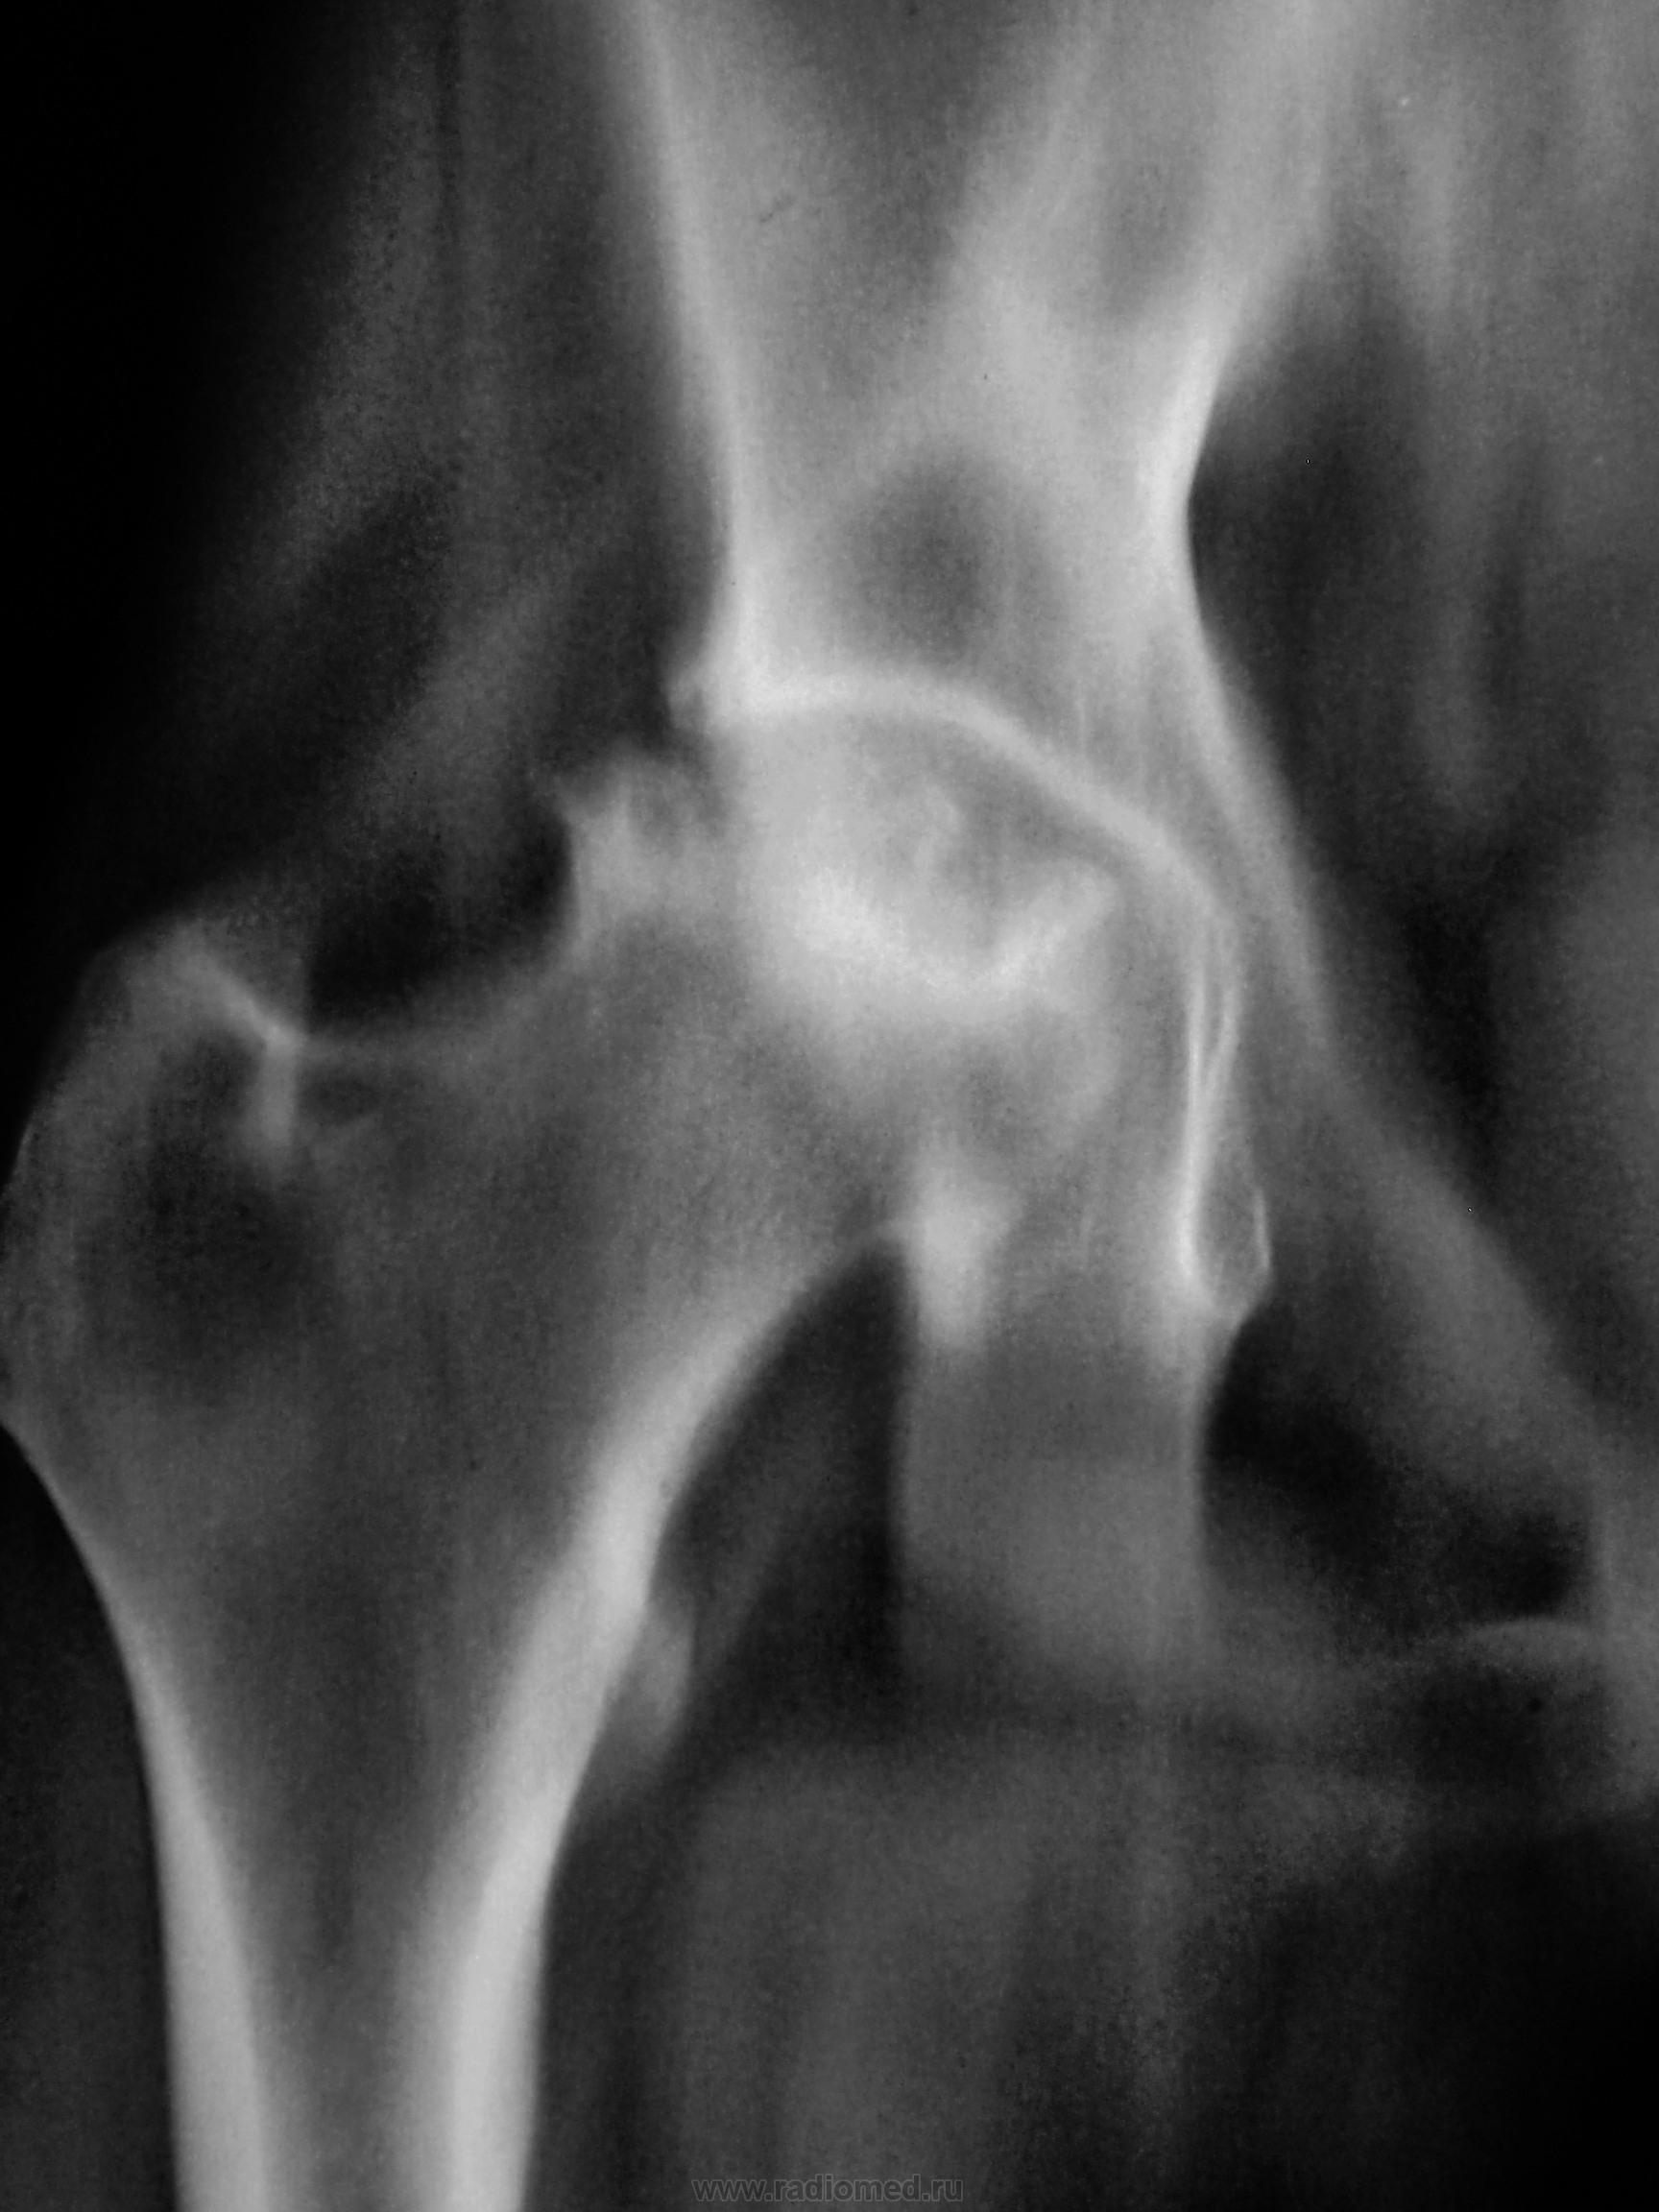

Пациент направлен на рентгенографию тазобедренного сустава и поясничного отдела позвоночника, в связи с имеющимися болями в тазобедренном суставе.

Пятнистая структура головки бедра. Особенно «загогулина» довольно чёткая в в/наружном квадранте не нравится.

Неоднозначно всё

Асептический некроз головки бедра?

Значит, об асептическом некрозе можно думать, или стопудово?

В Ваших условиях, я бы сделал обзорный снимок таза,с захватом обоих тбс- сравнить. Может пестрота все лишь суперпозиция.!?